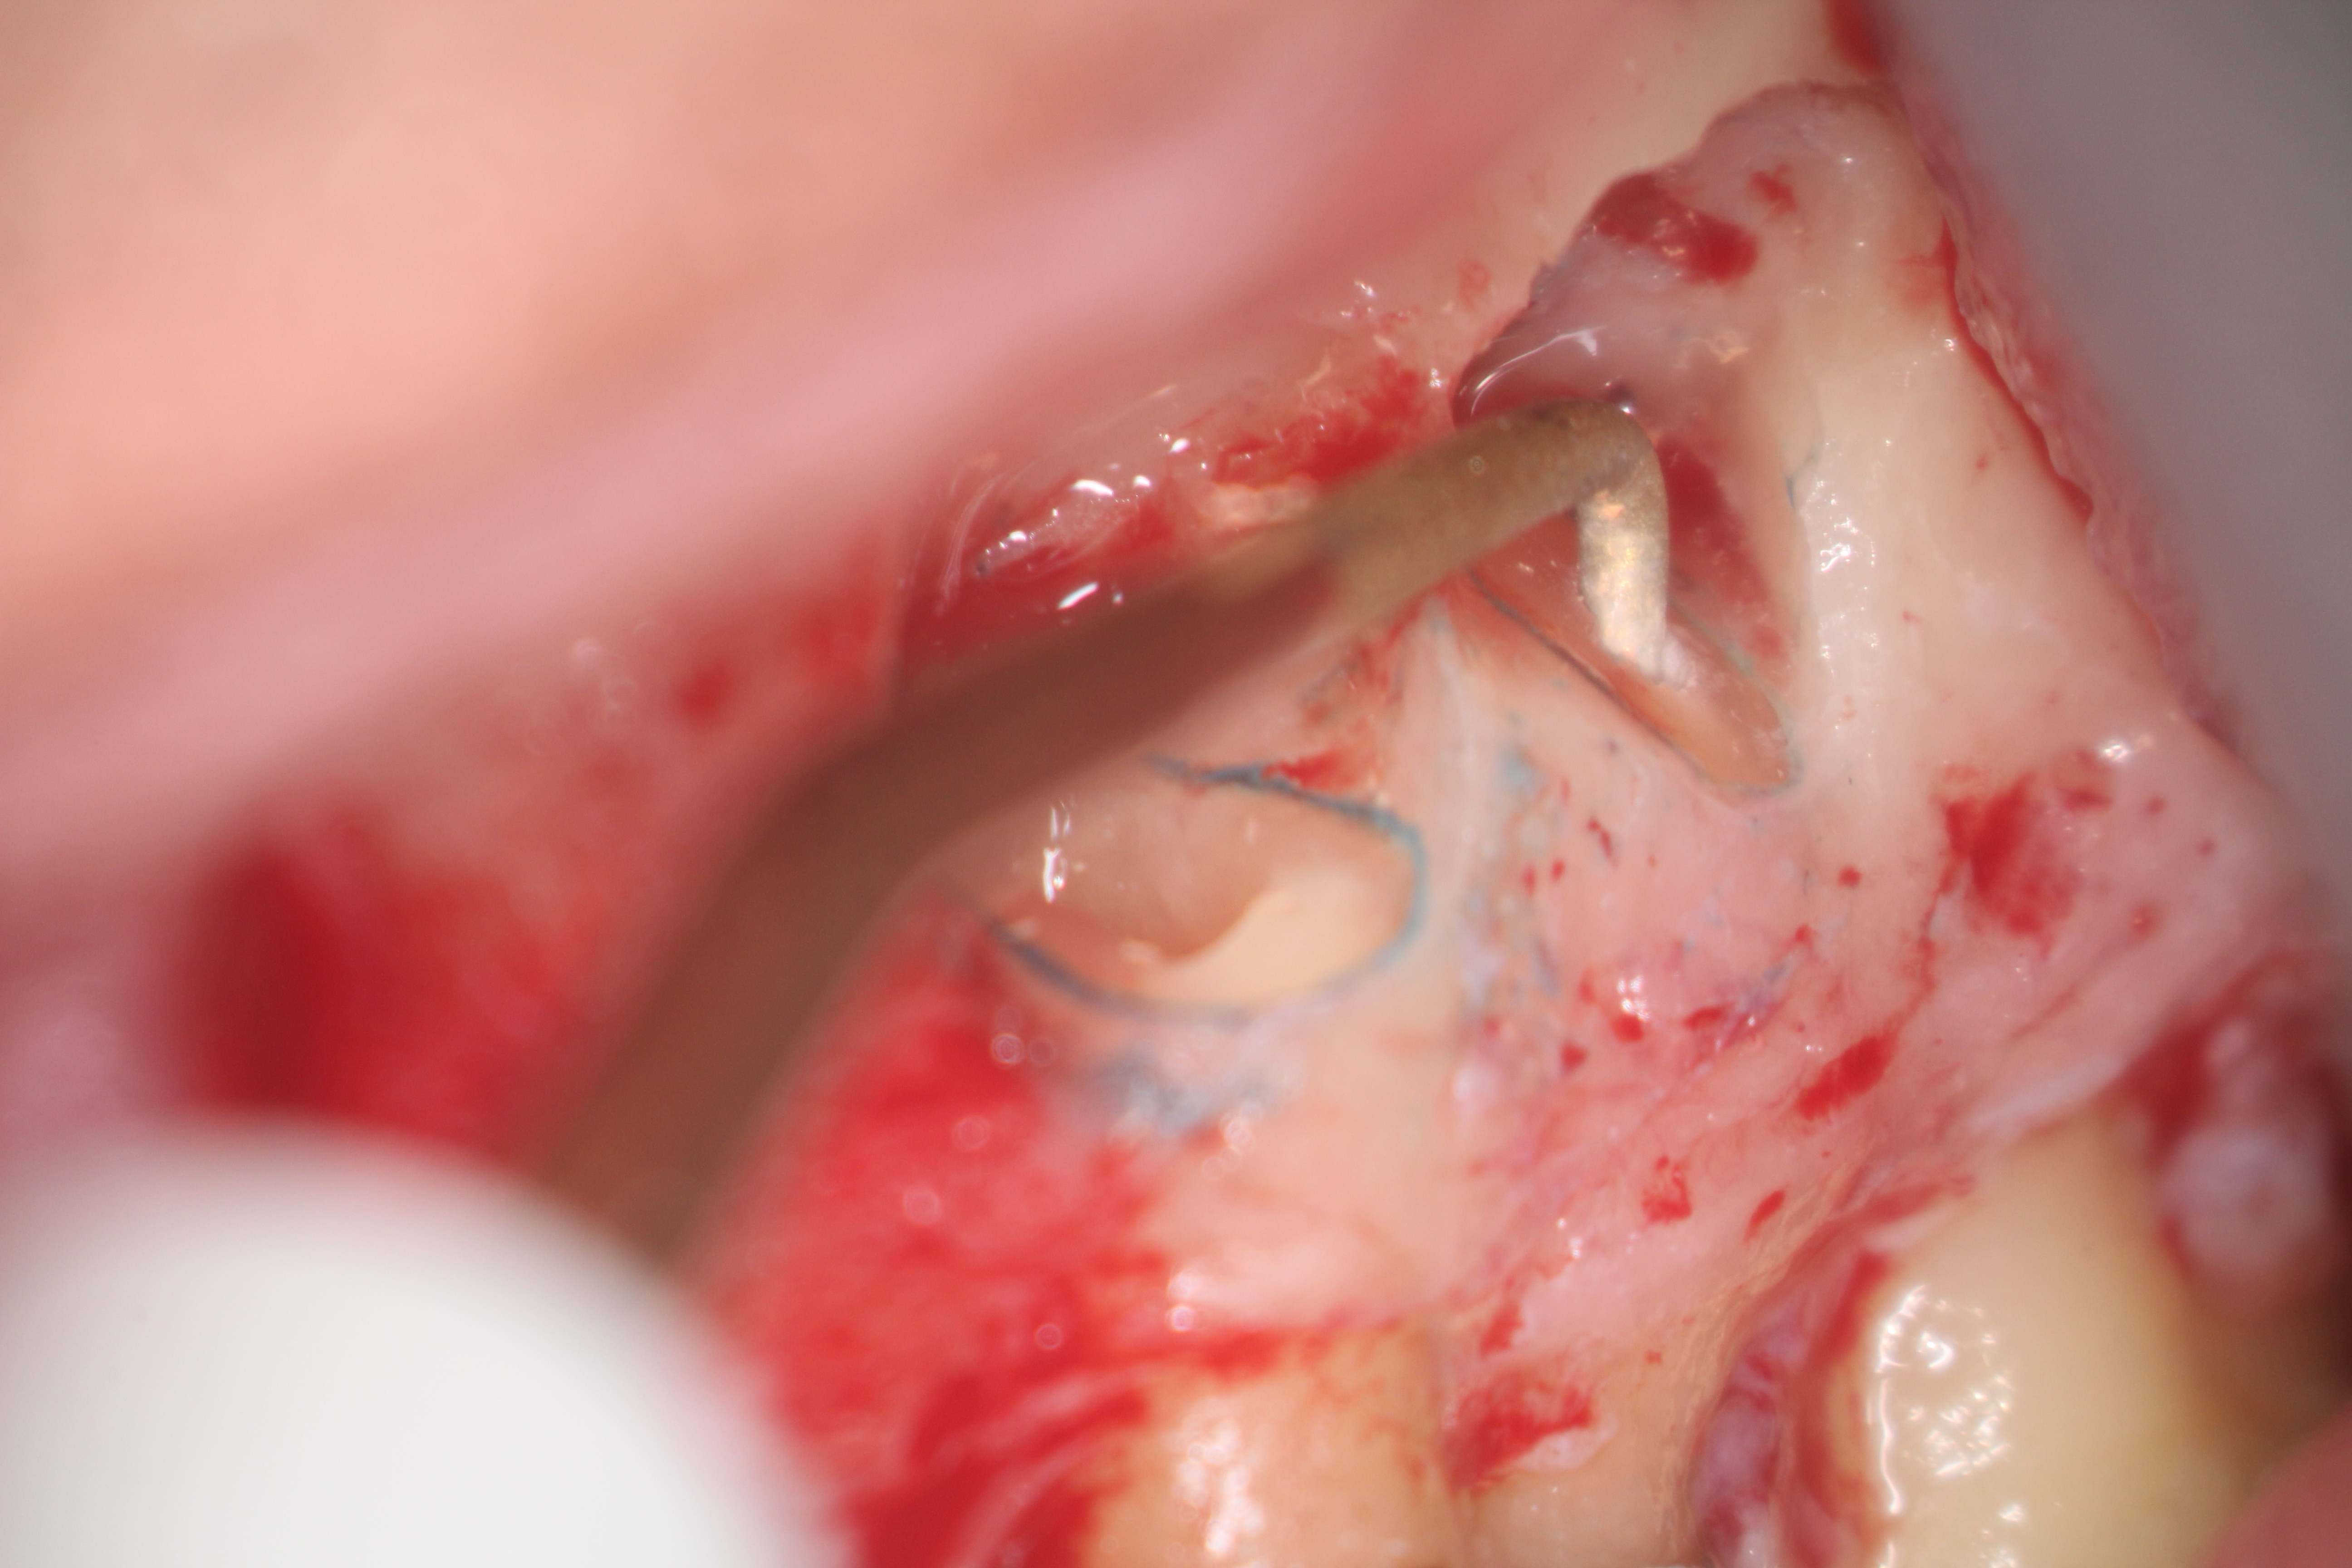

Fig 17. Retro-preparation with ultrasonic tip.

Figure 17

Clinical procedure: In the case of a root-end filling (Figure 15), once the apical 3 mm of the root has been resected (Figure 16) the canal system is then opened and cleaned with surgical ultrasonic tips to create the retro-preparation (Figure 17). After this is completed, the retro-preparation is dried and MTA is then placed and condensed in that space creating the retro-filling (Figure 18 through Figure 20).